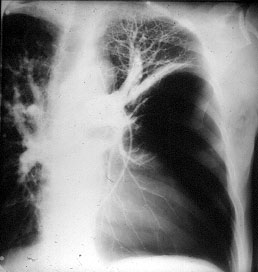

| Figure 3: Chest x-ray of a large bulla with true infection; after the appropriate medical treatment fever, hemptysis and fluid level persisted and the bulla was resected. |

Surgery is generally indicated to modify the functional status of the underlying lung by (1) relieving restrictive changes; (2) increasing compliance and airway caliber; (3) improving V/Q ratio; and (4) decreasing the physiologic dead space. These goals are easy to obtain in patients with enlarging bullae and minimal underlying lung disease. These are the best candidates for surgery and optimal results can be expected. Surgery is also indicated to treat complications related to the bullae, such as pneumothorax, true infection (Figure 3), hemoptysis, cancer (Figures 4, 5), and pain.